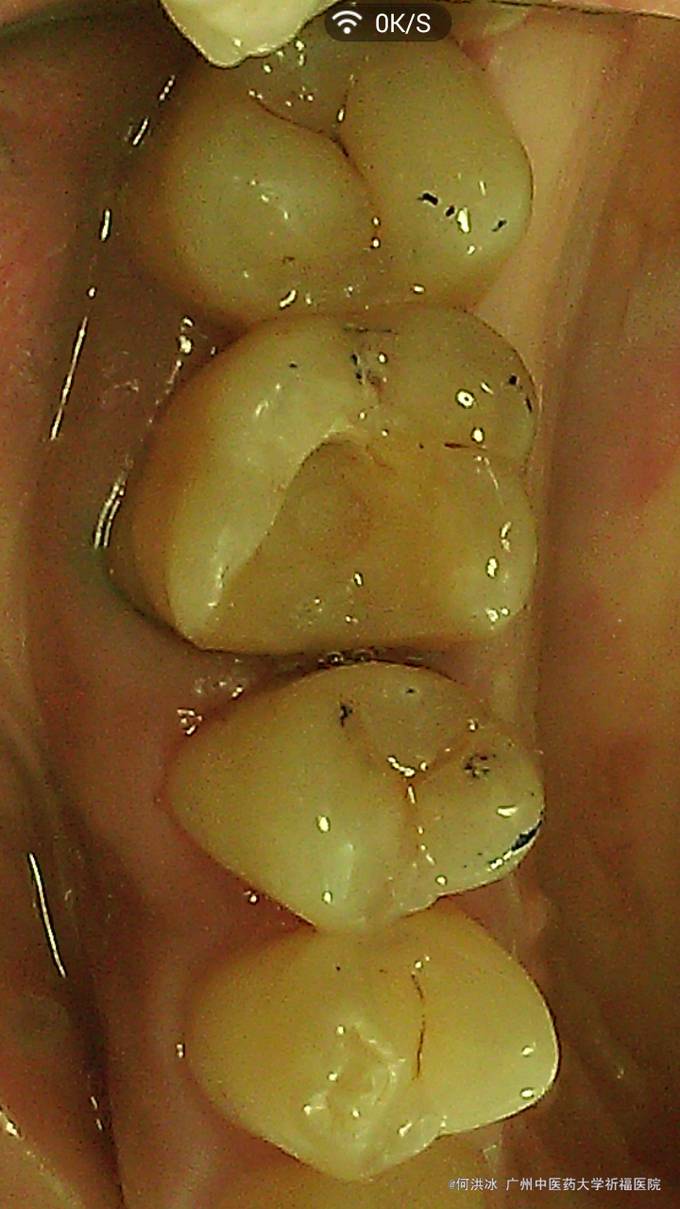

根据检查结果,提示,如冠修复,势必磨牙组织太多,更可怕的是,几乎全部釉质等坚硬组织可能去掉,这样基牙的抗力大大削弱。同时依据患者的要求,决定选用瓷嵌体修复。铸瓷价格偏高,病患没选择。 处理步骤: 1,牙周软组织准备,这一定要放在首位。去除结石,控制炎症。特别是判断生物学高度。避免后期的并发症。 2,硬组织准备:去尽腐质,薄壁弱尖,无基釉等。 3,寻找固位形,根管内,箱状等。 4,龈壁处理,这是最关键的部位,必要时使用“深部边缘提升”(Deep Margin Elevation,DME)。 5,垫底,填倒凹,结合流体树脂和通用树脂。 6,比色。本病例,因原牙体组织微发暗,色调不是太理想。 7,取精密印模。 7,试戴和粘固。

临床诊断不是太难。个人认为最关键的地方在以下几点: 1,牙周处理及生物学宽度考量。 2,硬组织的去除和保留。 3,比色有点难度。 4,粘接剂的选择。咱选用3M的小蜜蜂。当然用Varilink II最好。